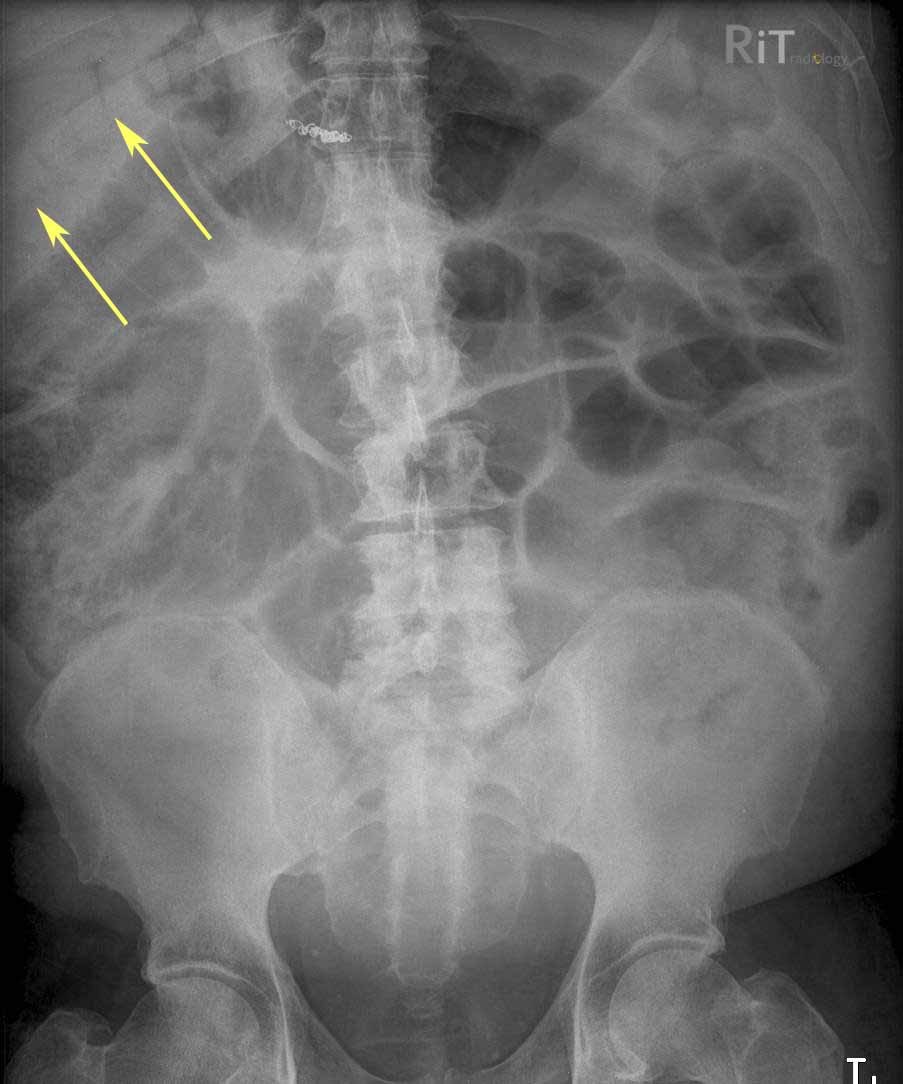

RiT Radiology December 2010